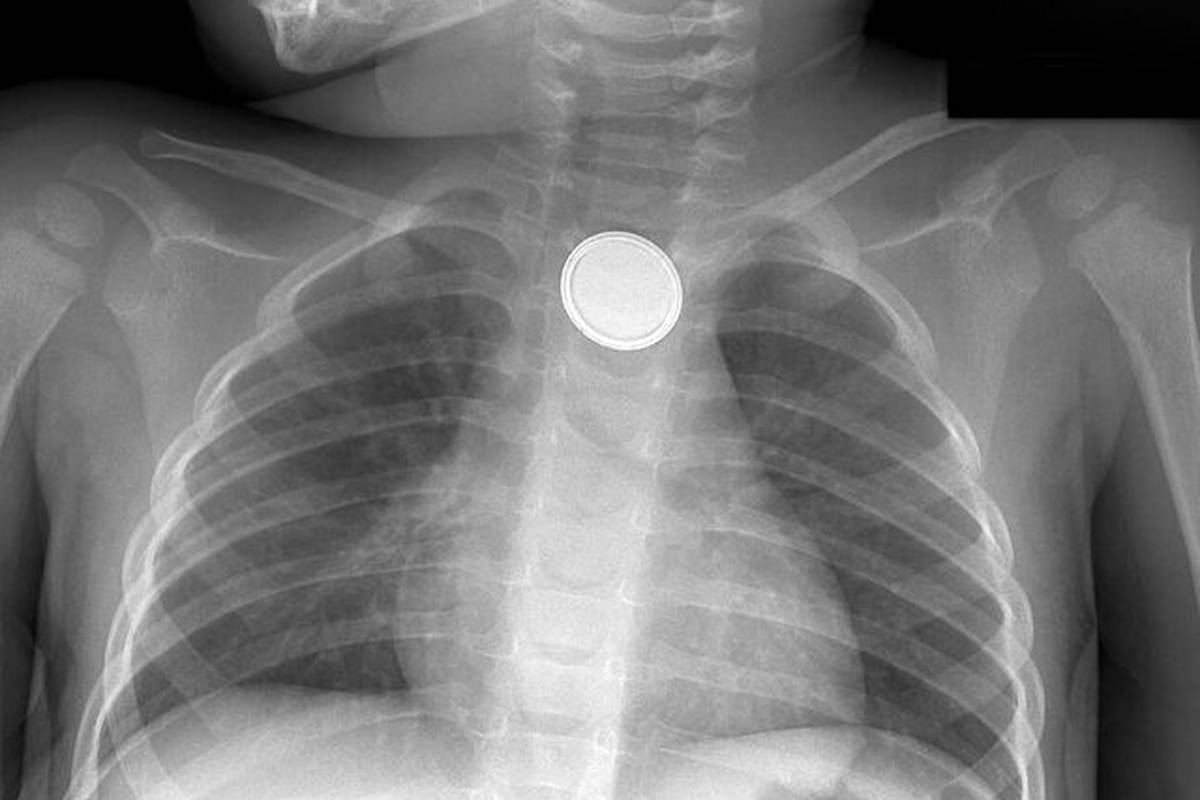

پس از رسیدن کودک به بیمارستان، ابتدا بررسی میشود که آیا باتری هنوز در مری گیر کرده است یا خیر سپس با استفاده از آندوسکوپ (Endoscope) باتری خارج میشود.